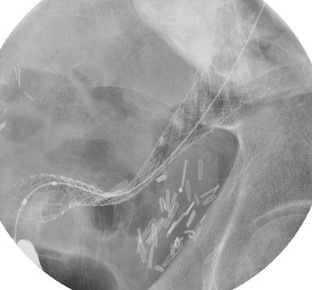

Self-expandable metal stent (SEMS) placement is a minimally invasive option for achieving acute colonic decompression in obstructed colorectal cancer. Colorectal stenting offers nonoperative, immediate, and effective colon decompression and allows bowel preparation for an elective oncologic resection. Patients who benefit the most are high-risk surgical patients and candidates for laparoscopic resection with complete obstruction, because emergency surgery can be avoided in more than 90% of patients. Colonic stent placement also offers effective palliation of malignant colonic obstruction, although it carries risks of delayed complications. When performed by experienced endoscopists, the technical success rate is high with a low procedural complication rate. Despite concerns of tumor seeding following endoscopic colorectal stent placement, no difference exists in oncologic long-term survival between patients who undergo stent placement followed by elective resection and those undergoing emergency bowel resection. Colorectal stents have also been used in selected patients with benign colonic strictures. Uncovered metal stents should be avoided in these patients, and fully covered stents are associated with high risk of migration. Patients with benign colonic stricture with acute colonic obstruction who are at high risk for emergency surgery can gain temporary relief of obstruction after SEMS placement; the stent can be removed en bloc with the colon specimen at surgery. This article reviews the techniques and indications of SEMS placement for benign and malignant colorectal obstructions.

Fig. 1

Fig. 2